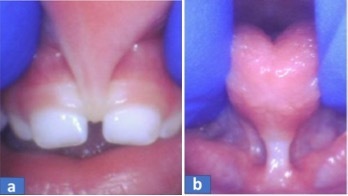

Gambar 2. Lip tie (a) dan tongue tie (b)

Gangguan anatomi organ

Contoh gangguan organ yang berhubungan dengan proses makan adalah tongue–tie dan lip–tie (Gambar 2). Kondisi tersebut dapat menyebabkan makanan sering “dilepeh”, “diemut” dan biasanya waktu yang lama untuk makan. Kondisi tersebut seringnya dibarengi dengan bicara yang tidak jelas.